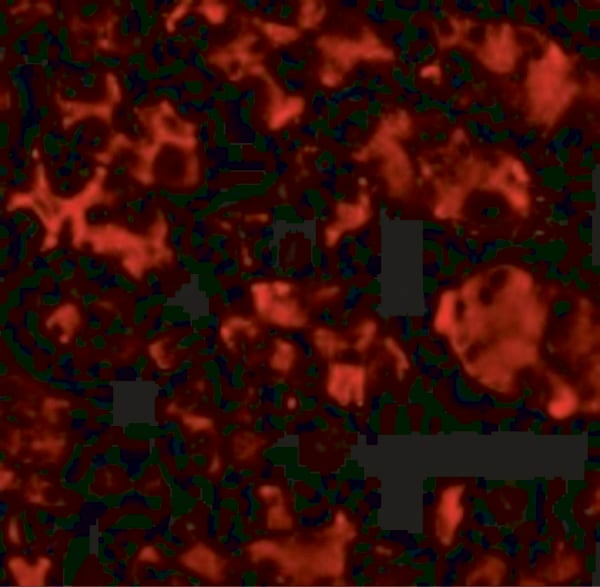

IHC (Immunohistochemistry)

(The image on the left is immunohistochemistry of paraffin-embedded Human cervical cancer tissue using AAA240305(ANKRD26 Antibody) at dilution 1/25, on the right is treated with synthetic peptide. (Original magnification: ×200))